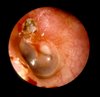

Presentation of OME.

A

Otoscopy findings:

- loss of light reflex

- opacification of ear drum

- retracted tympanic membrane

- air bubbles at tympanic membrane